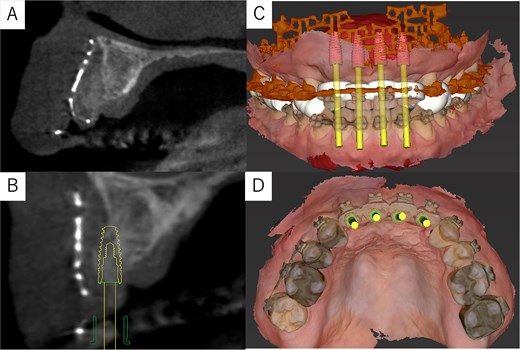

Simulation of dental implant placement in the maxillary anterior region using coDiagnostiX® (Straumann, Basel, Switzerland) revealed insufficient bone volume in both height and width (Fig. 3A). A 3D simulation was performed for bone augmentation in the maxillary anterior region alongside posterior mandibular movement. Mandibular retraction measured 6.2 mm on the right side and 7.0 mm on the left side. DICOM files from dental cone-beam computed tomography were converted to Standard Tesselation Language (STL) data using Volume Extractor® (Volume Extractor 3.0; i-Plants Systems Corporation, Iwate, Japan) (Fig. 3B). Osteotomy lines and the required bone augmentation were established using Geomagic Freeform® (3D Systems, Rock Hill, SC, USA) (Fig. 3C). A 3D model was printed (Straumann® CARES® P20+; Straumann, Basel, Switzerland) from the STL data, and a titanium mesh (Universal Mesh; Stryker Japan, Tokyo, Japan) was shaped to maintain space for PCBM grafting (Fig. 3D). The planned augmentation volume for implant placement was 5.6 mL, with a target bone harvest volume of 9 g, sourced from the right anterior iliac crest. In October 2023, SSRO and bone augmentation were performed simultaneously as planned (Fig. 4A). After harvesting PCBM from the right anterior iliac crest, SSRO was completed. The harvested PCBM was grafted into the bone defect and secured with the pre-bent titanium mesh (Fig. 4B). The wound was sutured, concluding the first operation.

Virtual maxilla reconstruction and SSRO procedures using computed tomography data. (A) Simulation of dental implant placement in the maxillary anterior defect using coDiagnostiX® revealed insufficient bone height and width. (B) Preoperative 3D images. (C) Osteotomy lines and the required bone augmentation were planned. (D) A 3D-printed model was created, and the titanium mesh was shaped to secure space for PCBM grafting.